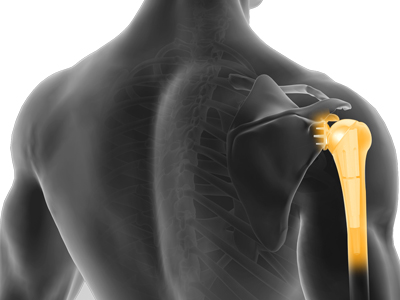

Shoulder Joint Replacement

Total shoulder replacement surgery is performed to relieve symptoms of severe shoulder pain and disability due to arthritis.

Reverse Shoulder Replacement

Conventional surgical methods such as total shoulder joint replacement are not very effective in the treatment of rotator cuff arthropathy.

Shoulder joint replacement is a surgical procedure that replaces damaged bone surfaces with artificial humeral and glenoid components to relieve pain and improve functional ability in the shoulder joint.